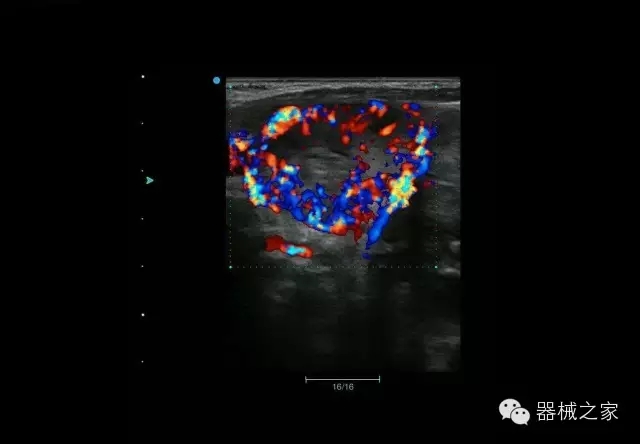

臨床圖片賞析

產(chǎn)品特點(diǎn)

·在便攜式緊湊平臺(tái)上采用更多倍波束并行接收信號(hào)處理模式,無論二維還是彩色血流圖像狀態(tài)下,擁有更靈敏的回波頻移捕獲能力,大大提高時(shí)間分辨率,尤其使得心血管表現(xiàn)更為突出;